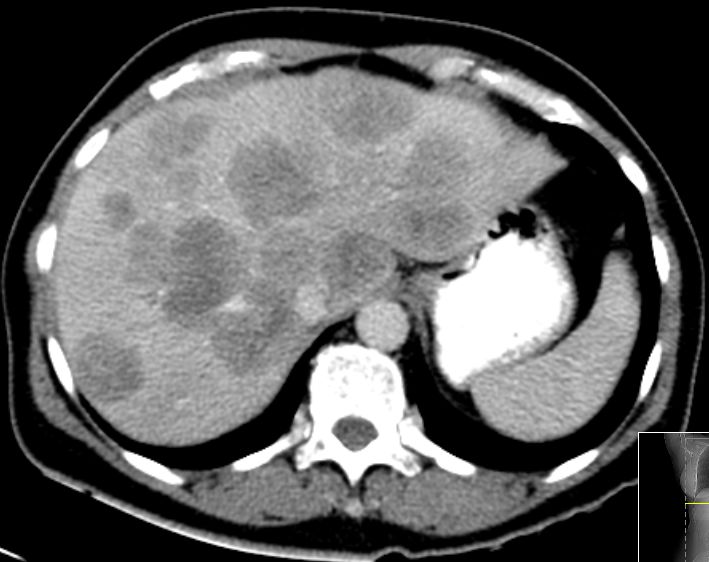

| CT | 61-jährige Frau mit Metastasenleber. Als Primärtumor wurde

ein Rektumkarzinom bei 8cm mit Lymphknotenmetastasen pararektal gefunden. Im

CT ohne KM sind keine Metastasen sichtbar.  | In der arteriellen Phase Unregelmäßigkeiten.  | ||

| In der portalvenösen Phase Metastasen gut

abgrenzbar.  | In der Spätphase verschwimmen die Konturen.  | |||